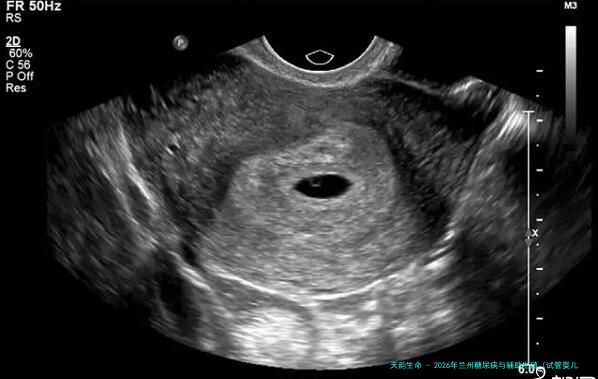

北京做三代试管能走医疗保险吗?试管婴儿技术已经发展到了第三代。越来越多的夫妻选择通过试管婴儿来完成生育愿望。然而关于众多家庭来讲,承担昂贵的费用成为了制约他们选择这项技术的主要因素其中一个。如此在北京地域做三代试管能否走医保呢?下方就让我们一起来了解一下。北京地区三代试管简介三代试管复被称为PGD(Preimplantation Genetic Diagnosis),是在人工授精的基础上结合遗传学